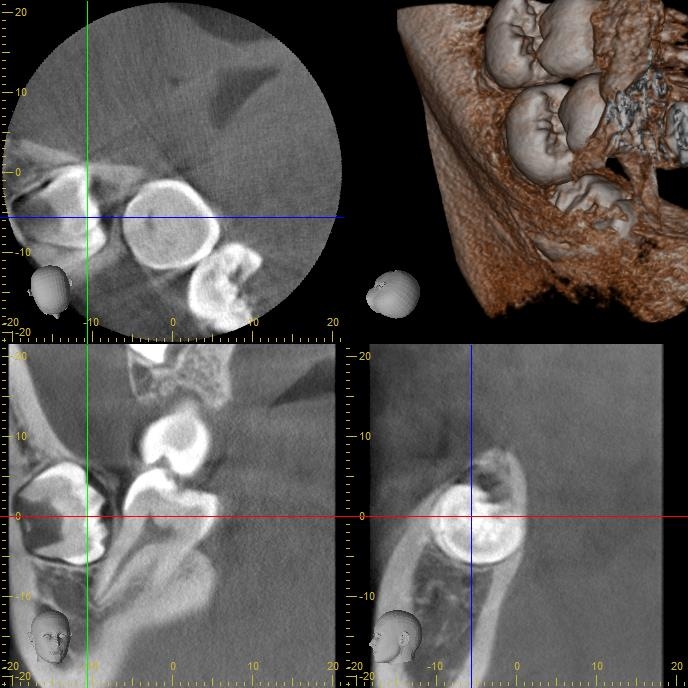

術前CT写真 (右下)

CT画像で状態を確認し、親知らずの歯根の曲がり具合や歯根の太さ、

下の親知らずの場合は下歯槽管神経との距離、

位置関係や骨の厚みなどを確認します。

下歯槽神経を傷をつけないように注意が必要です。

この場合、神経との距離を測り慎重に抜歯しないといけません。